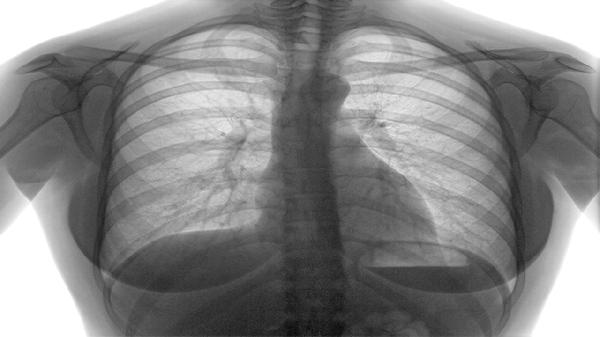

慢阻肺患者可通过腹式呼吸训练、缩唇呼吸训练、上肢力量训练、下肢耐力训练、平衡柔韧训练等方式进行锻炼。慢阻肺通常与长期吸烟、空气污染、反复呼吸道感染、遗传因素、职业粉尘接触等原因有关。